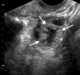

Corpus luteum cyst

A corpus luteum cyst is a type of ovarian cyst which may rupture about the time of menstruation, and take up to three months to disappear entirely. A corpus luteum cyst rarely occurs in women over the age of 50, because eggs are no longer being released after menopause. [Source: Wikipedia ]